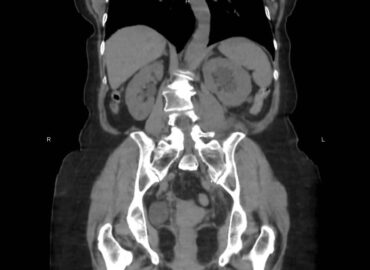

Paciente femenina de 60 años, consulta por dolor pelviano.